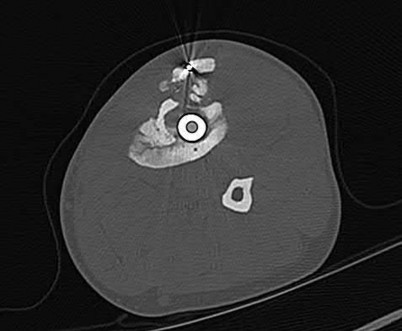

Which bone morphogenetic protein (BMP) is FDA-approved as an alternative to autograft for the treatment of acute, open tibial shaft fractures stabilized with an intramedullary nail?

Correct Answer: rhBMP-2

Explanation:

Recombinant human Bone Morphogenetic Protein-2 (rhBMP-2) is FDA approved for use in acute, open tibial shaft fractures stabilized with an intramedullary nail. rhBMP-7 (Osteogenic Protein-1 or OP-1) previously had a Humanitarian Device Exemption (HDE) for recalcitrant long bone nonunions but is no longer commercially available in the US for this indication.

Atypical femur fractures (AFFs) associated with prolonged bisphosphonate therapy have specific major criteria defined by the ASBMR. These include a location anywhere from just distal to the lesser trochanter to just proximal to the supracondylar flare, transverse or short oblique orientation, non-comminuted (or minimally comminuted), and originating at the lateral cortex with localized periosteal or endosteal thickening ('beaking').

Correct Answer: Transverse or short oblique fracture line originating at the lateral cortex with localized periosteal thickening (beaking)